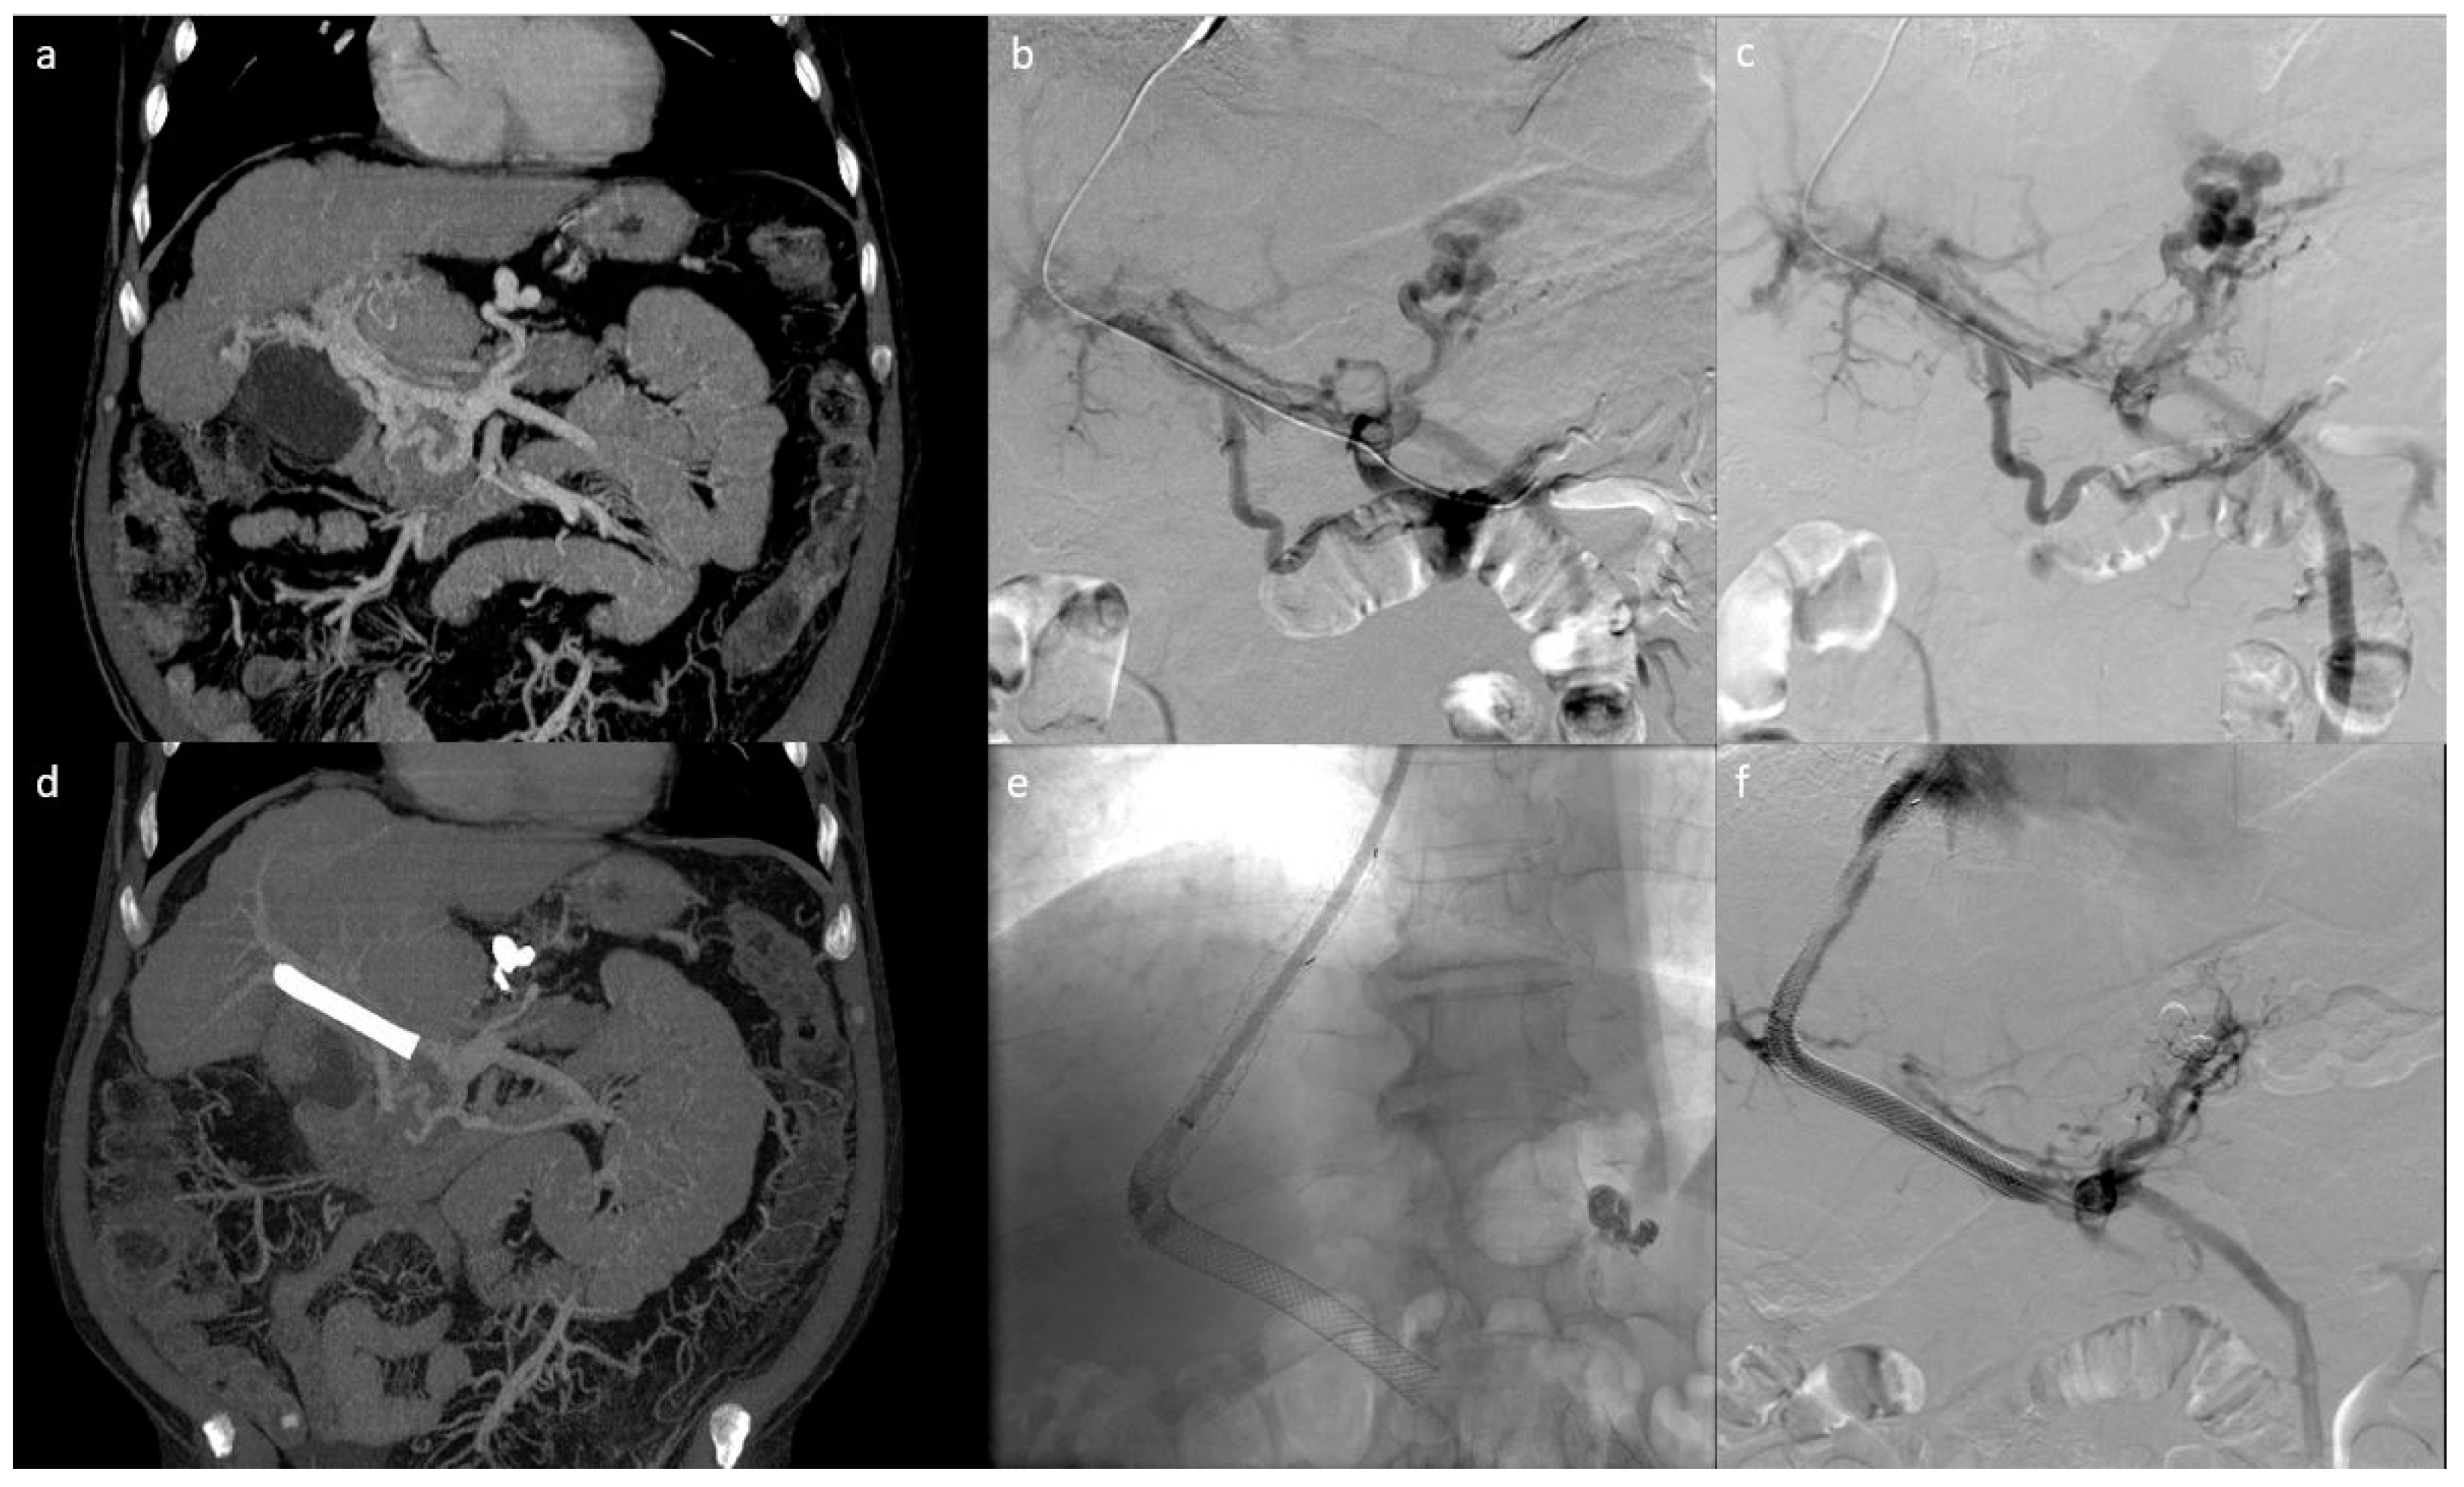

3. Results